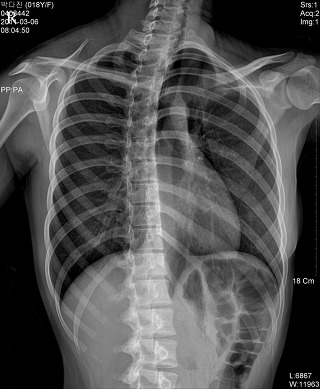

* CHEST PA (흉부 촬영)

♣검사목적

폐렴을 구분하거나 폐병소의 위치를 결정할 수 있다.

Position

환자는 가능한 Erect Position을 취한다.

턱을 격자 장치 위에 올려놓고 두부의 정중면이 수직으로 놓이게 한 다음 견갑골이 흉부 외측으로 회전되도록 손바닥을 위쪽으로 향하게 한 상태로 양손을 둔부 위에 올려 놓는다.

Check Point

양측 쇄골의 휴골단은(sternal end)은 척추로부터 같은 거리에 놓여야 한다.

3~5cm의 폐첨부(apex)가 쇄골위에 보여야 한다.

posterior rib이 diaphram위에 보여야 한다.

척추로 부터 늑골의 외측연까지 거리는 양측 모두 같아야 한다.

심장 음영의 일부가 척추의 오른쪽에 나타나야 한다

심장과 diaphram의 윤곽은 뚜렷해야 한다

흉추와 양측 rib의 희미한 음영(faint shadow)이 심장 음영을 통해 보여야   한다.